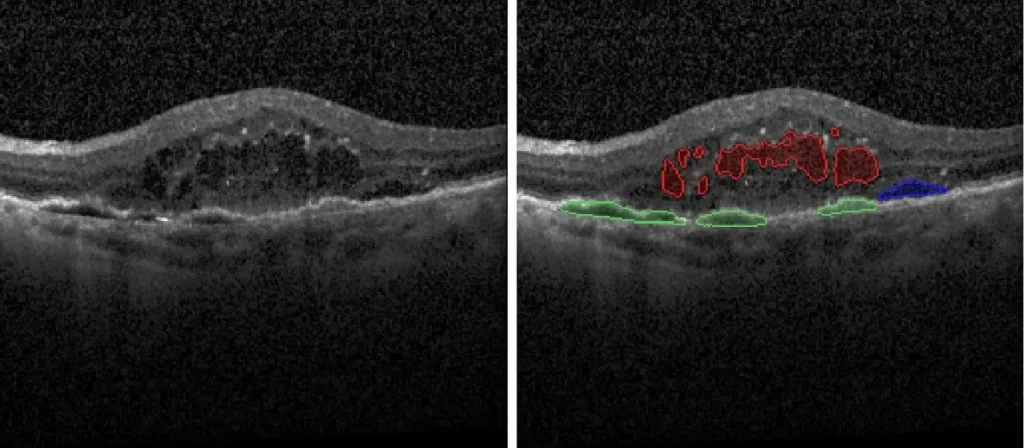

- Fluid Segmentation with Linear, Area, and Volume Quantification:

- Intraretinal Fluid (IRF)

- Subretinal Fluid (SRF)

- Pigment Epithelial Detachment (PED)

- Subretinal Hyper-Reflective Material (SHRM)